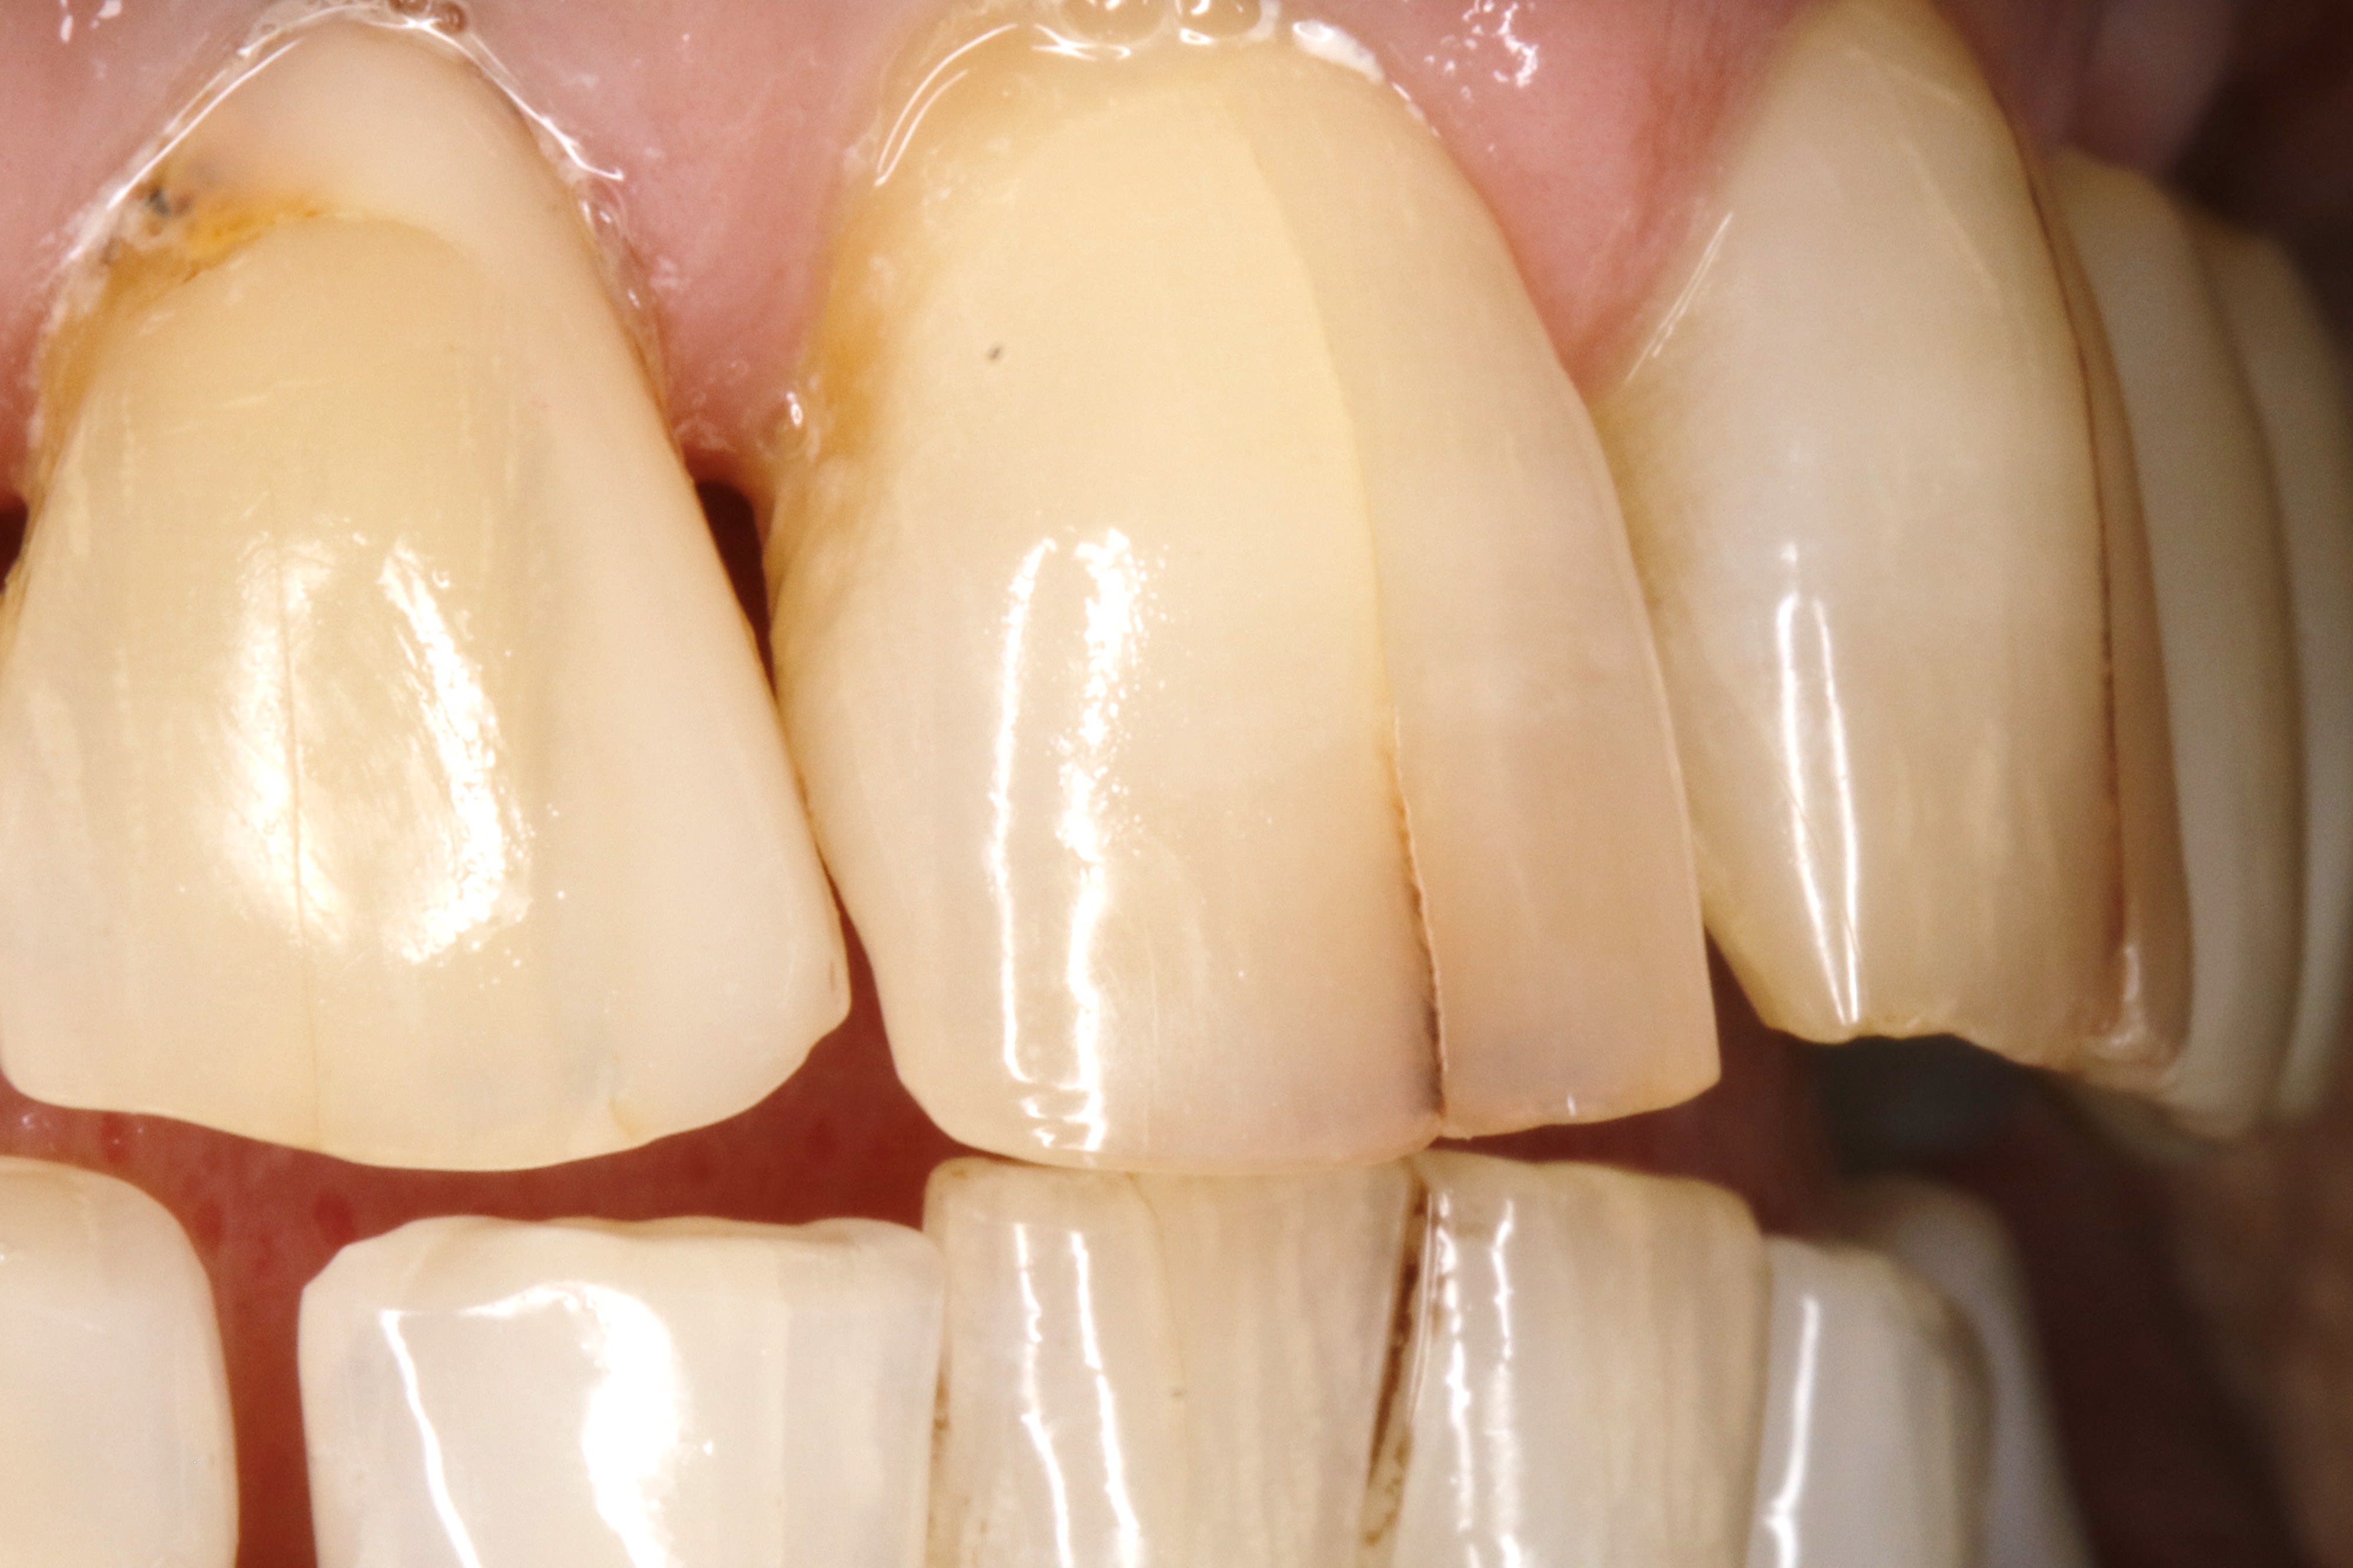

apres avoir lui avoir reglé la parafonction , , cette pré-mamie me demande de faire quelque chose pour ses fêlures pas jolies .

si je lui fais 2 facettes , comment gerer le prov ????

des idées sur la forme de préparation ?